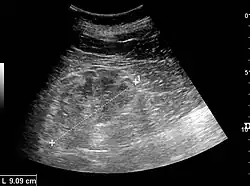

Ultrasound

Kidney ultrasonography is useful for diagnostic and prognostic purposes in chronic kidney disease. Whether the underlying pathologic change is glomerular sclerosis, tubular atrophy, interstitial fibrosis, or inflammation, the result is often increased echogenicity of the cortex. The echogenicity of the kidney should be related to the echogenicity of the liver or the spleen. Moreover, decreased kidney size and cortical thinning are often seen, especially when the disease progresses. However, kidney size correlates to height, and short persons tend to have small kidneys; thus, kidney size as the only parameter is unreliable.[63]

Chronic renal disease caused by glomerulonephritis with increased echogenicity and reduced cortical thickness. Measurement of kidney length on the US image is illustrated by '+' and a dashed line.[63] -